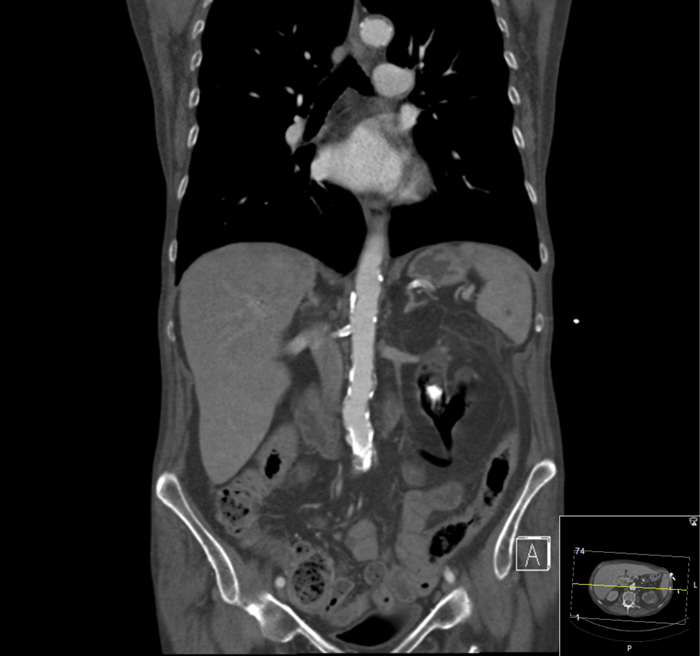

Case 1

A 78-year-old male was transferred from a referring hospital. He had a cystectomy and ileal conduit performed 15 years previously and had recently been admitted with a clinical diagnosis of an infected obstructed kidney. The referring hospital had sited bilateral antegrade ureteric stents and were unable to remove the stent on the left side when the sepsis had settled. He had a long tortuous ileal conduit which was difficult to endoscope. A safety guidewire was placed retrogradely into the left kidney and after considerable manipulation, the stent was removed but the wire displaced and could not be replaced. Interestingly, some of the strings were still attached to the proximal end of the stent which may have led to difficulty with extraction. A perioperative loopogram demonstrated free reflux up both sides and the patient made an uncomplicated recovery, stent free.

Figure 1: Perioperative loopogram. Red arrow - Foley catheter in long tortuous conduit. Green Arrow - reflux into right upper tract.